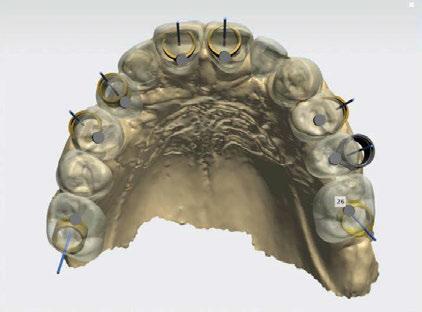

Diagnóstico y planificación digital

A tenor del estado oral proponemos múltiples opciones terapéuticas, consensuando entre paciente y facultativos una rehabilitación implantoprotésica fija superior e inferior. Debido a la lejanía de la residencia de la paciente, y motivados por las necesidades estéticas que esta exige, consideramos realizar una carga inmediata impresa con resina definitiva el mismo día de la cirugía. Tras el escaneado intraoral con el escáner Dexis IS3700 (Figuras 7 y 8) y realización de CBCT, subimos los ficheros a la plataforma Bego Guide,

31 Gaceta Dental · N o 366 | Mayo 2024 Caso clínico. CIENCIA Y CLÍNICA

Figura 3. Visión intraoral oclusal mandibular. Figura 4. Visión intraoral frontal. Figura 1. Visión intraoral oclusal maxilar. Figura 2. Visión lateral izquierda intraoral. Figura 7. Escaneado intraoral maxilar con Dexis IS3700. Figura 8. Escaneado intraoral mandibular con Dexis IS3700. Figura 5. Visión extraoral lateral sonrisa.